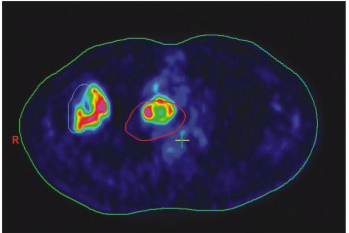

4、 放療及介入治療的精確定位

經(jīng)過PET-CT檢查可以清晰地顯示腫瘤的精確位置和腫瘤病灶的大小,根據(jù)PET-CT技術(shù)可以使放療醫(yī)師全面了解病灶的代謝情況,及時(shí)制定新的治療計(jì)劃,按腫瘤的生物靶區(qū)進(jìn)行治療,并且可以通過使用不同的示蹤把腫瘤泛氧狀態(tài)和細(xì)胞增殖狀態(tài)表現(xiàn)出來,對病人適形調(diào)強(qiáng)治療起到首要的指導(dǎo)作用。從而提高了治療的效果又同時(shí)減低了治療的副作用。很多的研究表明PET-CT將對放射及介入治療產(chǎn)生重大影像。

生物靶區(qū)與CT靶區(qū)明顯不一致(紅線區(qū)域?yàn)镃T靶區(qū))。

18F-FMISO與FLT檢查對照的乏氧細(xì)胞顯示圖